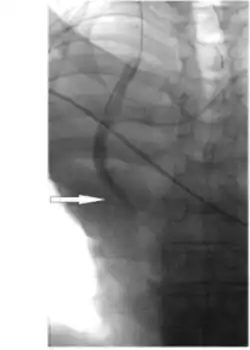

Hydrophilic catheter treatments can also be used through placement of the catheter through the femoral veins to access the stenosis in the vena cava to measure haemodynamic and angiography. [6] Angiography allows for visualisation of the stenosis in the vena cava and measurements of the pressures and length of narrowing can be obtained from the technique, including the narrowest diameter of the stenosis. [6] Balloon angioplasties can also be performed in the narrowed vena cava using Sterling balloons. [6] Dilations are also performed with higher pressure Dorado balloons, using the same wire as the Sterling balloon. [6] Sustained results of increased flow and significant reduction in obstructions following stent implantation occurs from balloon angioplasty treatments. [6]